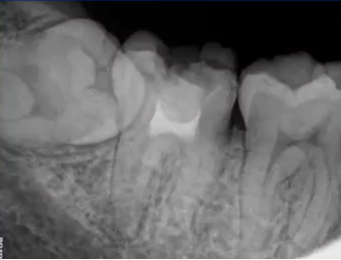

32岁,男性,因咬物不适来院就诊。

查:14残根,牙龈红肿;35叩诊(+),45叩诊(+),牙颌面见畸形中央尖。

35叩诊(+)

二次拍根尖片确认可看到根尖低密度炎症,临床检查与影像学检查相符,是根尖周炎。

曲面断层片怎么看口腔精读 | 一次性教你看懂曲面断层片!_https://www.jmylbn.com_新闻资讯_第21张

临床检查时发现14残根,牙龈红肿。曲面断层片上由于前磨牙转角问题,看不到残根,无法明确到底有没有残根,无法通过曲面断层片进行确诊或评估。

曲面断层片怎么看口腔精读 | 一次性教你看懂曲面断层片!_https://www.jmylbn.com_新闻资讯_第22张

这时需要加拍根尖片,很明显能看到残根。这就说明,有曲面断层片也不能排除情况。

曲面断层片怎么看口腔精读 | 一次性教你看懂曲面断层片!_https://www.jmylbn.com_新闻资讯_第23张

临床检查45叩诊(+),牙颌面见畸形中央尖。加拍根尖片可看到,右下5根方有低密度影,并且右下5的牙根较短小,和曲面断层片上显示的大小不同,所以右下5是舌向倾斜的牙齿。